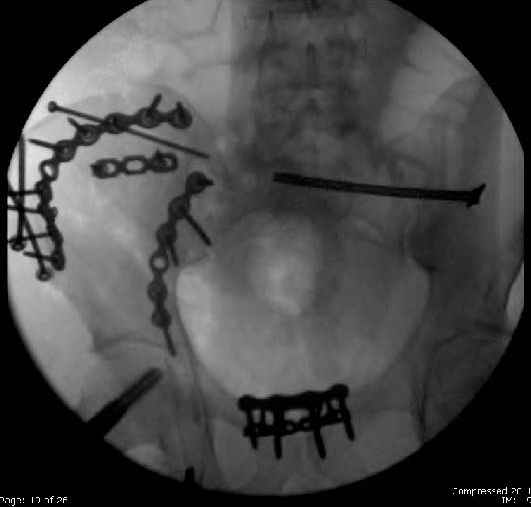

Here are the postop fluoros.

First exposed symphysis & clamped w/Faraboeuf as close to anatomic as possible.

Then extended to R ilioinguinal,really just the lateral window.

Reduced the triangular wedge piece of iliac wing to posterior intact ilium (crescent), held w/k-wire, then used 3-hole push plate to keep from moving, lagged from lat-med w 3.5 screw.

Then 6-hole plate along brim with 1 screw in R sacral ala. Then lagged 2 screws along crest A --> P. finally 10-hole plate along inner aspect of crest. R posterior ilium still a bit stepped off.

Symphysis then 'fine-tuned' & reduced as close as possible to anatomic (but, still with forward rotation of R hemipelvis - or, is it extension?) Accepted that amount of deformity and plated symph

with 4-hole symphyseal plate.

Fluoroed L SI joint and it seemed stable, but wide. So, applied c-clamp to try to squeeze down L SI joint (and note, on the last slide attached, that it's still wide), and got it closer. Single perc Iliosacral screw 40mm thread.

Applied second plate anteriorly on symphysis as I wasn't confident L SI was as stable as it could be and wanted to protect it better.